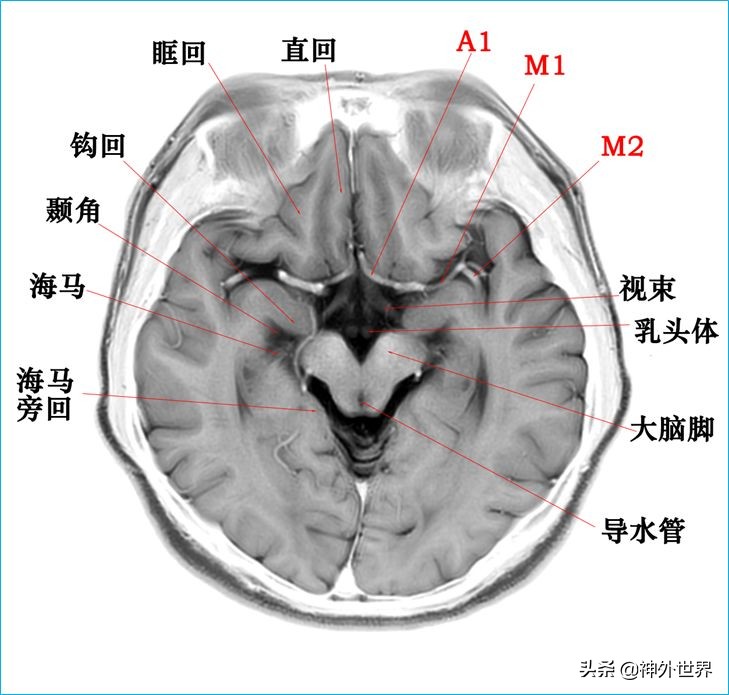

四、T2WI反相图学颅脑断层解剖

以下图片均来自我院3.0T核磁共振的T2WI反相图。标注均为我自己完成,水平有限,难免有误,还望各位老师多多指正。谢谢。